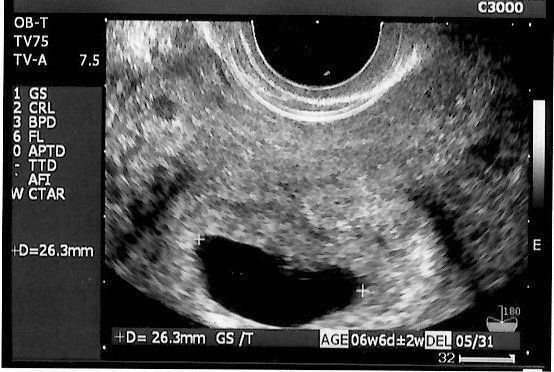

ママにエールさんの妊娠6週目のエコー写真

薄茶色のおりもの(出血)があり、気になって産院へ電話。「とりあえず、診察へ」と言われて受診しましたが、妊娠初期によくある程度の出血だから大丈夫とのこと。出血止めの薬だけ処方されました。ちょうどこの時、エコーで白い小さな粒を確認。「これが赤ちゃんに成長していきます」と先生に聞いて、愛しさでエコー写真をしばらく眺めていました。夫に見せたら、「ちっこい」と笑っていました。